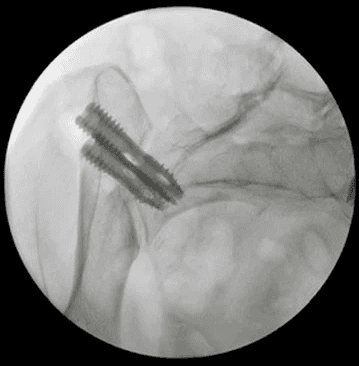

Posterior oblique Lateral